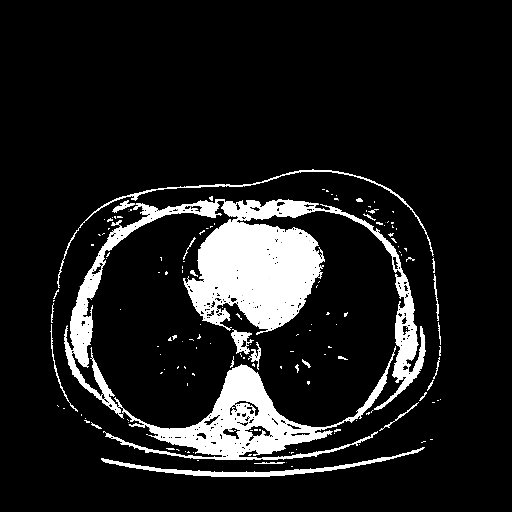

Generated VENOUS CT scan (A→B translation)

Full window (WL 1023.5, WW 4095 β†’ Low βˆ’1024, High +3071)

Actual HU range: [-1024.0, 3071.0]